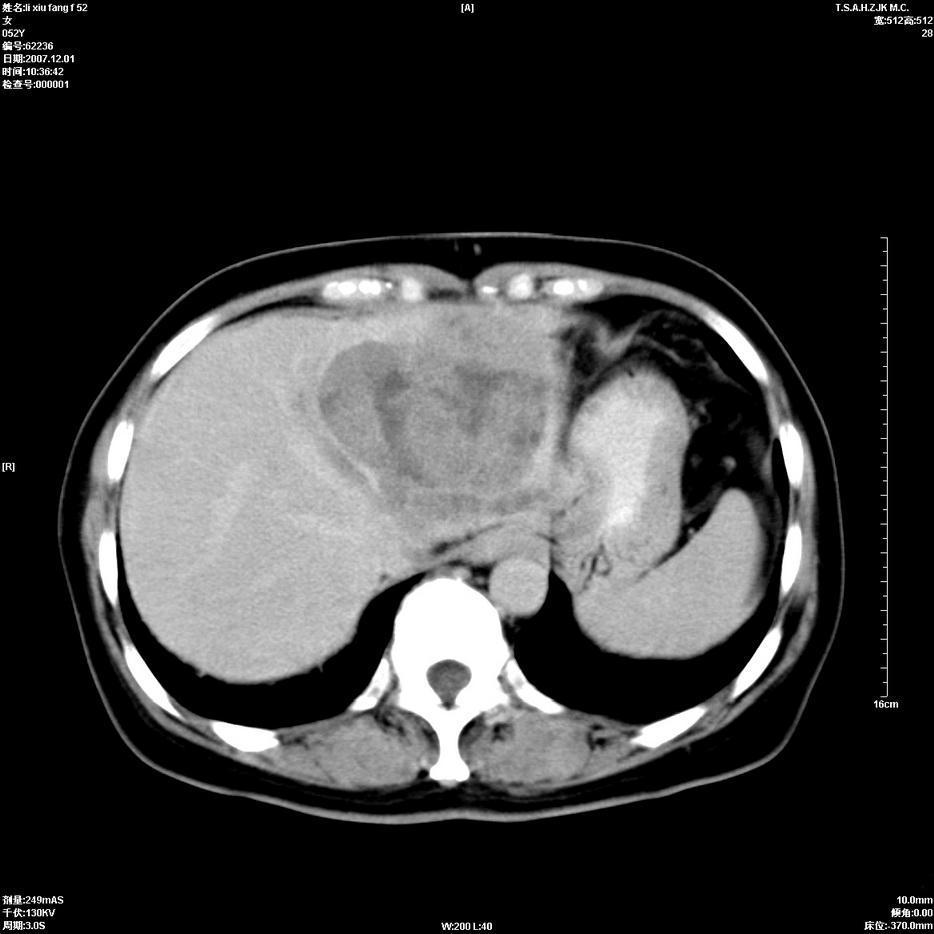

标题: CT12858:女,52岁,胎甲球蛋白861肝左叶占位,肝癌。下腔静 [打印本页]

标题: CT12858:女,52岁,胎甲球蛋白861肝左叶占位,肝癌。下腔静

肝左叶巨大低密度灶肿块,增强符合快进快出表现,有动静脉交通支;静脉期,下腔静脉内有充盈缺损,afp明显升高,支持肝癌并下腔静脉癌栓形成。

以下是引用拾荒者在2008-4-15 22:57:00的发言:[br]肝左叶巨大低密度灶肿块,增强符合快进快出表现,有动静脉交通支;静脉期,下腔静脉内有充盈缺损,afp明显升高,支持肝癌并下腔静脉癌栓形成。